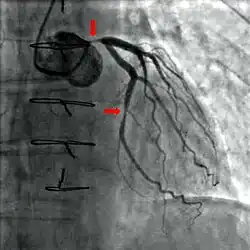

A coronary angiogram (an X-ray with radiocontrast agent in the coronary arteries) that shows the left coronary circulation. The distal left main coronary artery (LMCA) is in the left upper quadrant of the image. Its main branches (also visible) are the left circumflex artery (LCX), which courses top-to-bottom initially and then toward the centre/bottom, and the left anterior descending (LAD) artery, which courses from left-to-right on the image and then down the middle of the image to project underneath the distal LCX. The LAD, as is usual, has two large diagonal branches, which arise at the centre-top of the image and course toward the centre/right of the image.